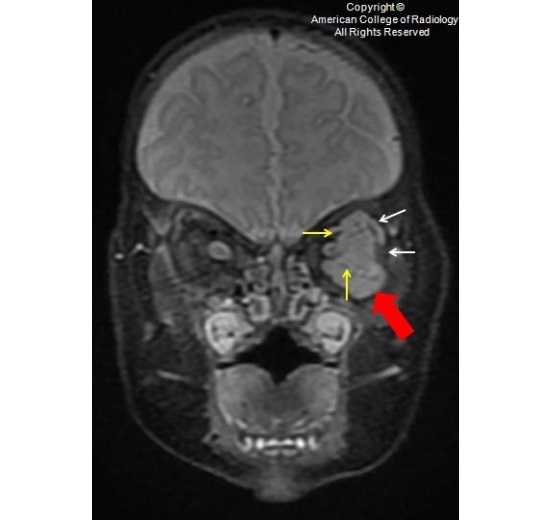

图 2 为 T2,眼眶内可见一均匀长 T2 信号(红圈),未侵及眶内肌肉和神经(白色箭头)。外前方可见一流空信号(黄色箭头)

图 3 为 T2,眼眶内可见一均匀长 T2 信号(红圈),未侵及眶内肌肉和神经(白色箭头)。外前方可见一流空信号(黄色箭头)

图 4 为冠状压脂强化 T1,可见一均匀强化的分叶状眶内肿块(红色箭头),完全包绕视神经(红圈),可见血管流空信号(黄色箭头)